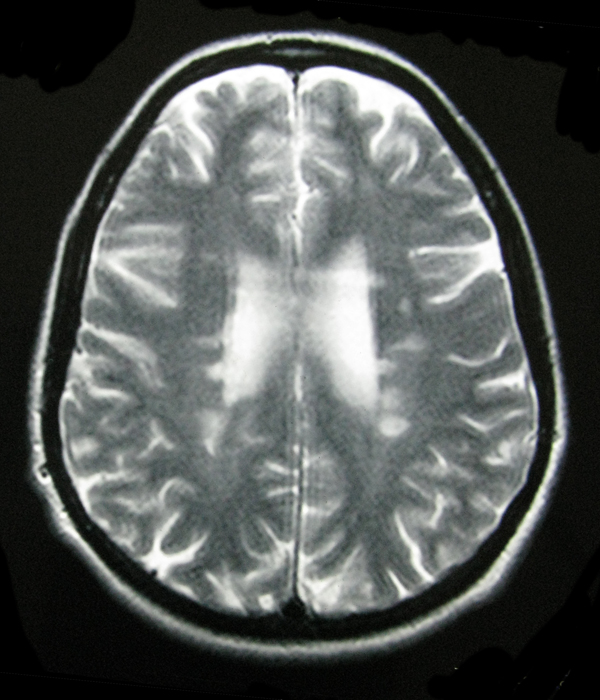

- My Brain in 2009